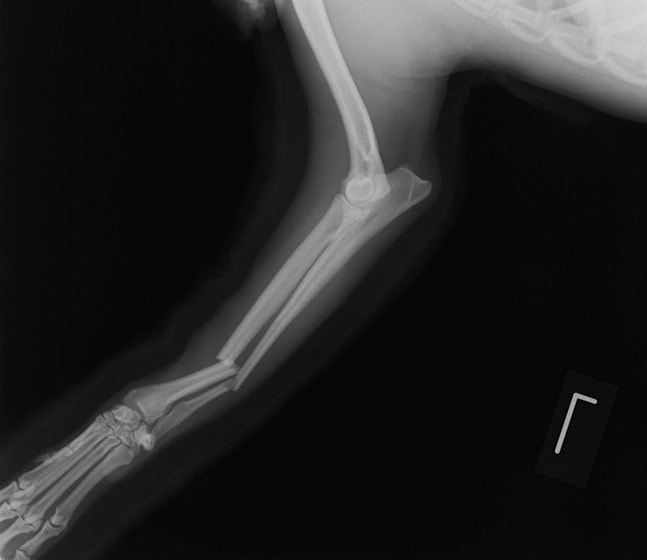

ペルシャ猫 11ヶ月齢 雄

他院にて左大腿骨遠位の成長板骨折(salter-harrisⅠ型)が認められており、治療相談を目的として来院。当院にて、キルシュナーワイヤーを用いたピンニングにより骨折部位の整復を行いました。術後の経過は良好で、現在も経過観察中です。

術前レントゲン

術後レントゲン

Arthrex社のターゲティングデバイスを用いてピンニングの位置を調整することで、確実な固定を行っています。当院ではこの手術器具以外にも、人の手術にも使用される様々な器具を導入し、手術精度を高め、また医療メーカーと新しい器具の開発、試作にも取り組んでおります。